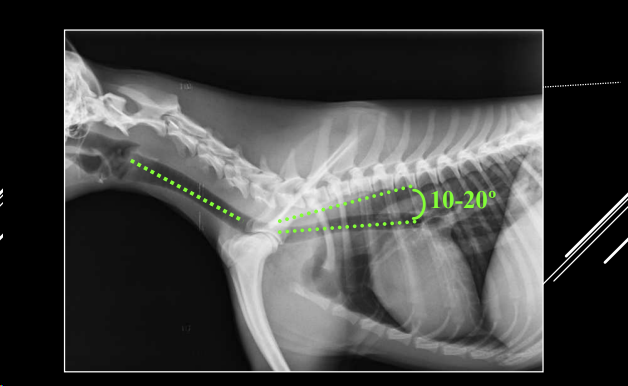

TRÁQUEA

- Proyección LL.

- Cabeza y cuello rectos (evitar hiperextensión).

- Divergencia 10–20° con raquis torácico.

Alteraciones detectables:

- Desplazamientos (dorsal o ventral).

- Dorsal: cardiomegalia, masa craneoventral.

- Ventral: dilatación esofágica, masa craneodorsal.